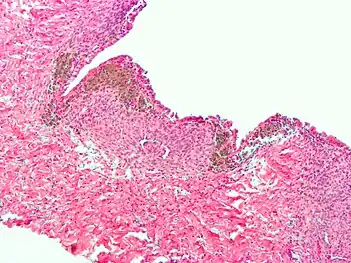

Histopathology

For a histopathological diagnosis, at least two of the following three criteria should be present:[88]

Immunohistochemistry has been found to be useful in diagnosing endometriosis as stromal cells have a peculiar surface antigen, CD10, thus allowing the pathologist go straight to a staining area and hence confirm the presence of stromal cells and sometimes glandular tissue is thus identified that was missed on routine H&E staining.[89]